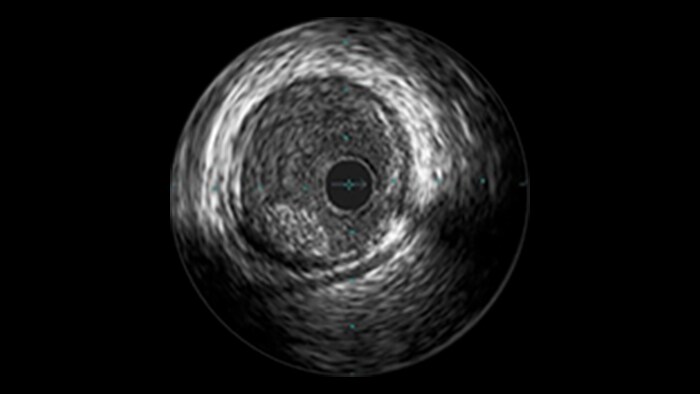

IVUS

Intravascular ultrasound (IVUS) provides images from within the vessel to accurately assess and optimize your treatment plan.